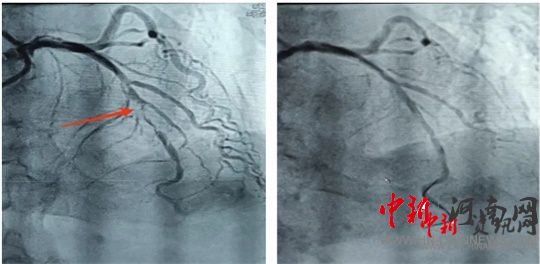

術(shù)前 術(shù)后

造影結(jié)果顯示,前降支中段次全閉塞。經(jīng)過充分預(yù)處理病變后,應(yīng)用一枚藥物球囊進行治療。隨后,患者癥狀明顯緩解,生命體征恢復(fù)平穩(wěn),送入重癥監(jiān)護室進行過渡觀察。